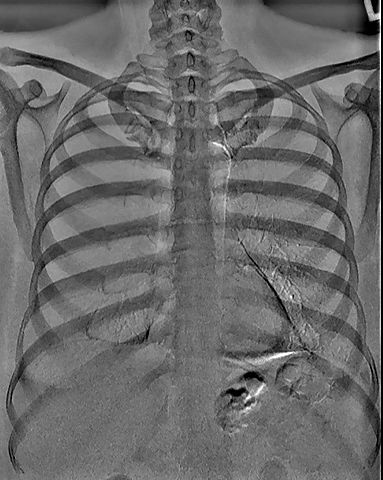

• Tomografía Computarizada

Tomografía Computarizada

La tomografía computarizada fue creada por Godfrey Housnfield.